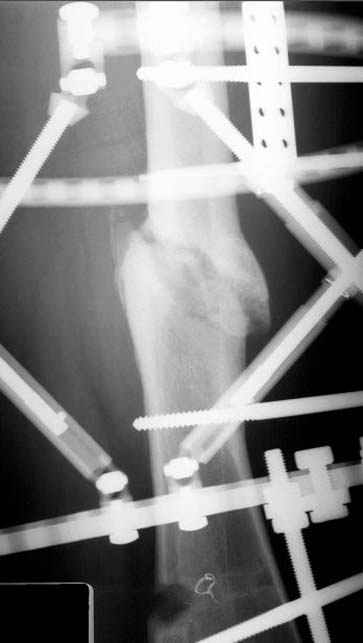

пластическая модель; и коррекция бедра аппаратом Илизарова.

Имею другие снимки тоже, получится как отчет о моей работе.

хотя даже если бы и инфекция , то nail exchange с рассверливанием канала - вариант дебрайдмента) Я думаю, что последовательность развития событий:

Узкий к-м канал - тонкий гвоздь- усталостный перелом дистальных винтов - развитие нестабильности и как ее результат остеолиз вокруг гвоздя - деформация анатомической оси бедра. Похоже, что я понял почему аппарат, а не новый гвоздь:-)

ЕТ - Изначально костно-мозговой канал бедра был узкий, дальнейшее его рассверливание ещё больше скомпрометирует прочность бедра( латеральный кортекс дистального отломка уже истончен), приведет к дефекту наружной стенки - хотя это только мои догадки - хотелось бы знать мнение Джолдаса о выбранной тактике.